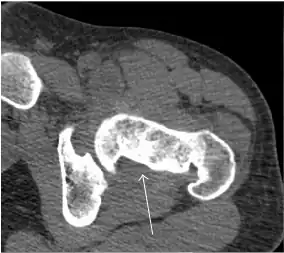

Synovial chondromatosis can be confidently diagnosed by X-ray when calcified cartilaginous chondromas are seen. However, other synovial proliferative processes, such as pigmented villonodular synovitis, require MRI for accurate diagnosis, although noncalcified synovitis can be suspected in radiographs by indirect signs, such as soft tissue swelling and/or erosions in the femoral head, femoral neck, or acetabulum (Figure 7).[1]

Figure 7:

-

Axial CT image of pigmented villonodular synovitis eroding the posterior cortex of the femoral neck.[1] -

Sagittal T2* gradient echo image showing a posterior soft tissue mass with hypointense areas secondary to hemosiderin deposition.[1] -

In synovial proliferative disorders, MRI demonstrates synovial hypertrophy. In the case of PVNS, characteristic foci of low signal intensity related to hemosiderin deposition are better seen on gradient echo T2* images (Figure 7). In the case of synovial osteochondromatosis, the synovial hypertrophy is accompanied by intermediate signal cartilaginous loose bodies and/or low signal calcified loose bodies.[1]